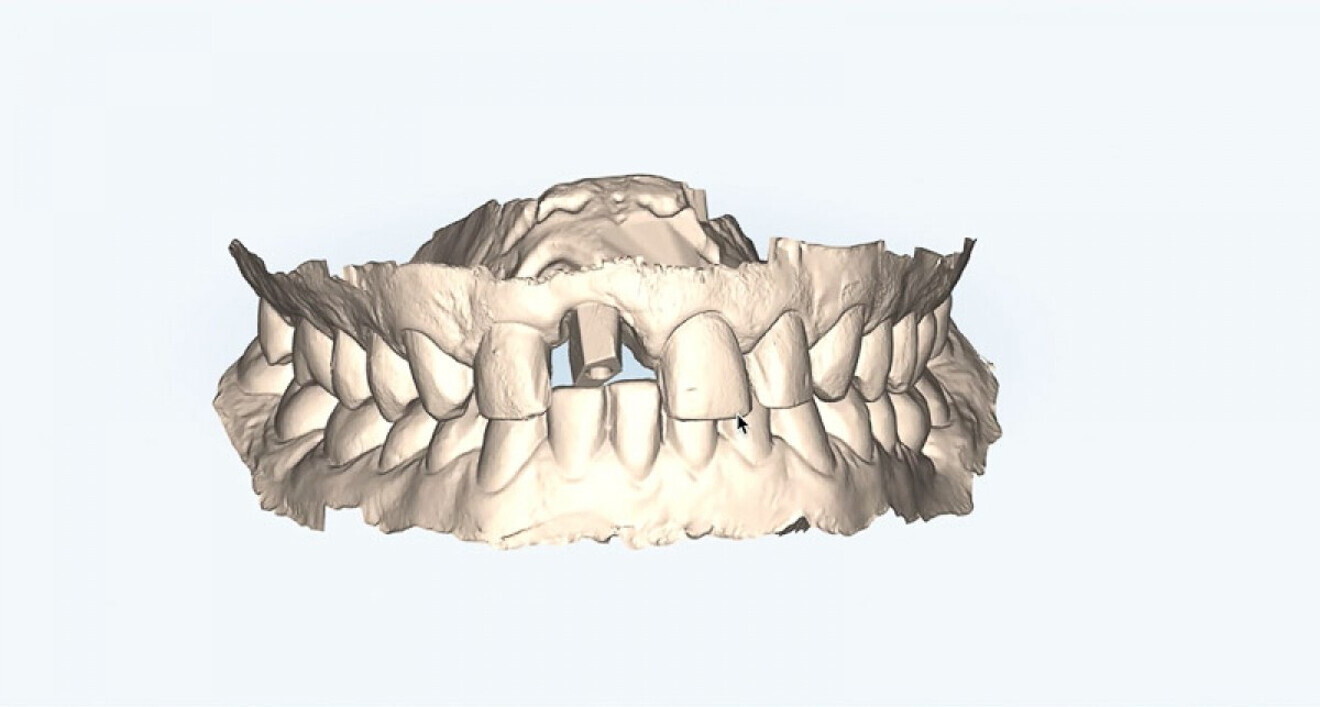

Met de iTero- scanner werd een intraorale scan gemaakt en via de Invisalign Practice App konden zowel intra- als extra-orale beelden worden verzameld.

Daarna worden de foto’s en scans geüpload op het Invisalign-platform. Ook wordt aangegeven welke elementen bij de restauratieve fase worden betrokken.

Wanneer de behandelaar de uitvoering van alle vereiste bewegingen heeft beoordeeld, kan hij de aligners aanvragen. Nadat de orthodontische behandeling is voltooid, kan men verdergaan met de restauratieve behandeling, altijd via een volledige digitale workflow (afb. 8, 9).

Afb. 9